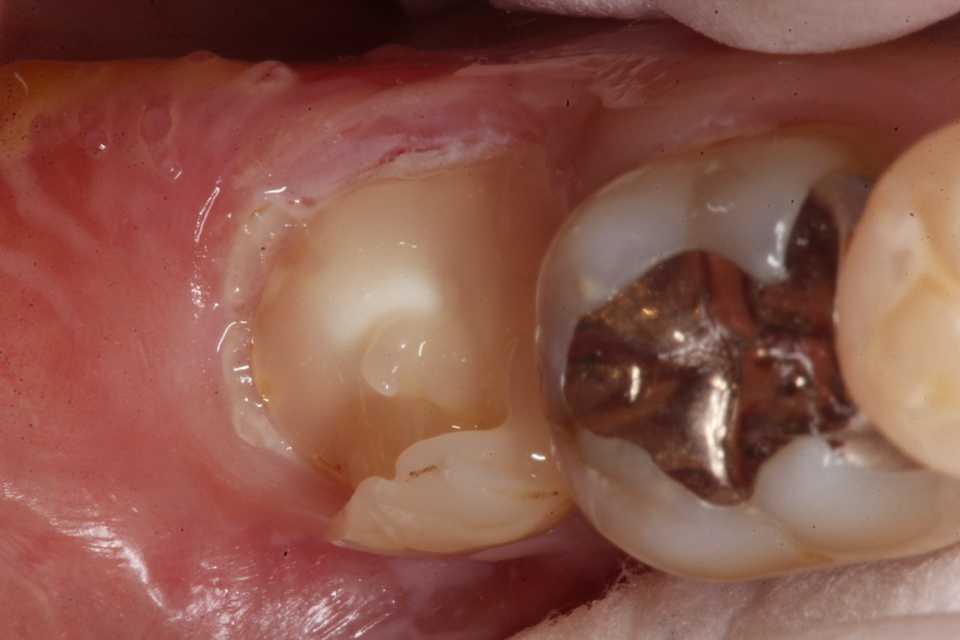

ストリップスを使わない隣接面CR(ダイレ… 2025.11.26

ストリップスを使わない隣接面CR(ダイレ… 2025.11.07